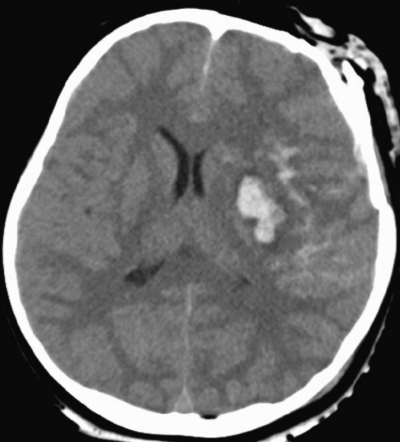

来院時、意識レベルは GCS5 (E1V1M3)。体温 36.8 ℃。心拍数 90/分、整。血圧 134/86 mmHg。呼吸数 22/分。SpO2 100 %(バッグバルブマスク人工呼吸下)。左瞳孔の散大と対光反射消失とを認める。左前頭部に開放創を認め、骨折部と連続している。頭部 CTを別に示す。

治療として適切なのはどれか。2つ選べ。

a. 減圧開頭術

b. 抗菌薬投与

c. 脳室ドレナージ

d. 脳内血腫除去術

e. 副腎皮質ステロイド投与